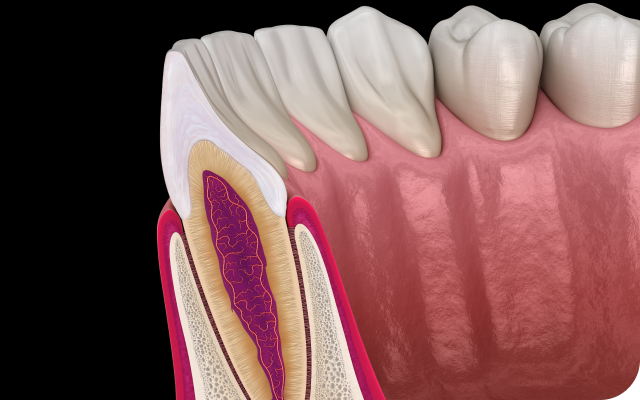

One day Implant

치주염 치료, 치아를 오래 쓰기 위한 바른 시작

STEP 01

건강한 잇몸

치주염 치료01

초기에 건강한 잇몸이며

연분홍색을 띱니다.

화살표

정기적인 관리

STEP 02

치은염

치주염 치료02

칫솔질을 할 때 피가 나거나

잇몸이 붓습니다.

스케일링

STEP 03

초기 치주염

치주염 치료03

염증으로 인해 잇몸이 내려가며

쉽게 피가 나기 시작합니다.

치근활택술/치주소파술

STEP 04

진행된 치주염

치주염 치료04

잇몸이 심하게 붓고 뿌리가

드러나 치아가 흔들립니다.

치주수술